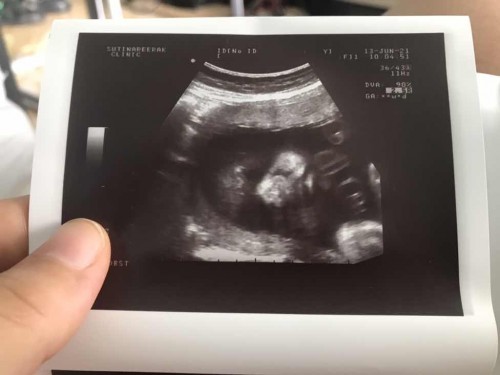

วันนี้ไปหาป้าหมอมาครับ💖 29w 6d น้ำหนัก 1,416กรัม

บ้านนี้ไปมาเพิ่งกลับค่ะ 24 week 1 day 759 กรัมค่ะ😊